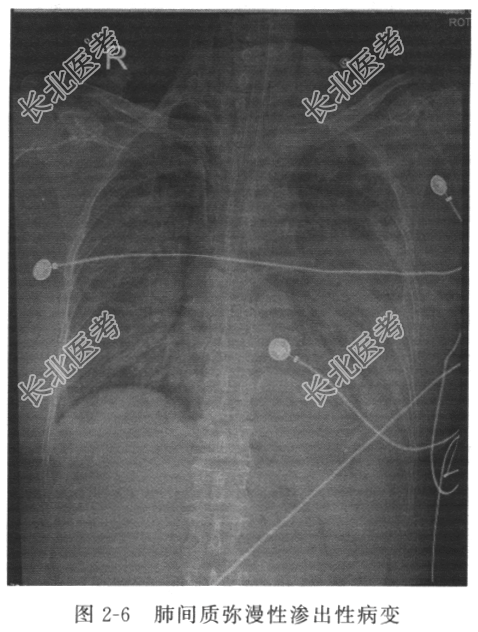

病情 患者女性,63岁,因“反复咳嗽6年,气促3年,加重1个月,摔倒致右股骨颈骨折后呼吸困难2天余”入院,诊断为“干燥综合征,肺间质病变并感染,肺动脉高压”,予以积极抗感染、降低肺动脉压、止咳、平喘等对症支持治疗后,患者咳嗽、咳痰明显好转。2天前,因摔倒致右股骨颈骨折后呼吸困难逐渐加重,为加强监护及治疗进入ICU。 护理体查 T 36.4℃,P 110次/min,R 44次/min,BP 138/85mmHg,SpO

92%。持续泵入镇静药镇静,保留经口气管插管,呼吸机辅助呼吸[PEEP 15cmH

O,吸入氧浓度(FiO

)60%],实施肺保护性通气,双肺呼吸音粗,可闻及湿啰音和哮鸣音,双下肺呼吸音低。 辅助检查 床旁胸部X线片(图2-6)示双肺呈“白肺”改变,较前明显进展。血气分析示pH 7.46,PaCO

63mmHg,PaO

64mmHg,BE 18.6mmol/L。

入院诊断 急性呼吸窘迫综合征(ARDS);干燥综合征,肺间质病变并感染;股骨颈骨折。